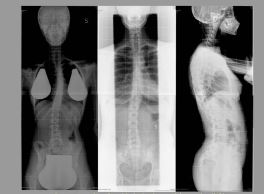

This is easily observable comparing the X-ray images results, shown in figure 20, where tipycaly positioning and technical mistakes are present, and the one shown in figure 21, where those mistakes are not present.

Figure 20:Examples of avoided mistakes: pelvis rotation (left) aperture (centre) upper limbs positioning (right).

Figure 21:Examples of correct imaging: AP (left) LL (right).